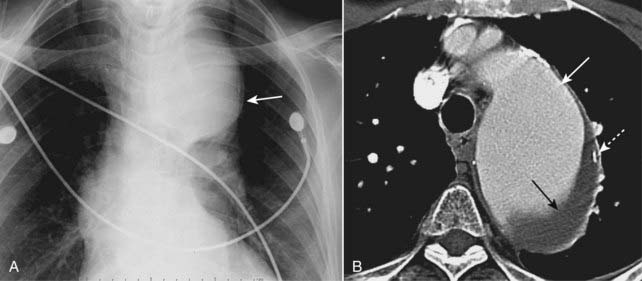

image Abnormal accumulations of fluid begin in the dependent portions of the pericardial space, which, in the supine position, is posterior to the left ventricle (Fig. 9-2A).

image As the pericardial effusion increases in size, it tends to accumulate more along the right heart border until it fills the pericardial space and encircles the heart (Fig. 9-2B).

image

Figure 9-2 Pericardial effusions, small and large.

A, Fluid first begins to accumulate in the dependent portions of the pericardial space which is posterior to the left ventricle in the supine position (solid white arrow). B, As the effusion increases in size, it fills the pericardial space and encircles the heart (dotted white arrows). Conventional chest radiographs may show an enlarged cardiac silhouette but cannot differentiate the density of the heart from the effusion.